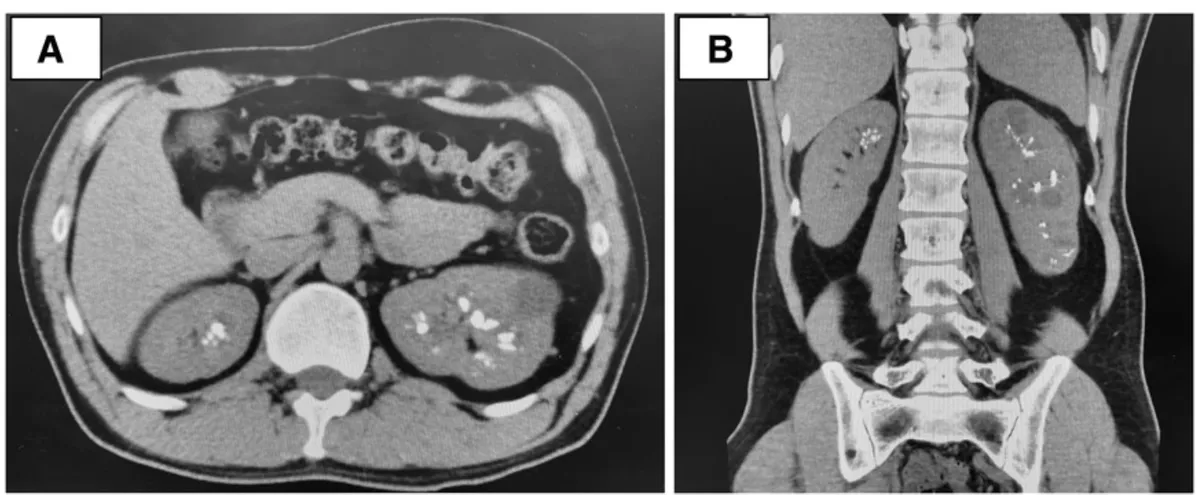

Os achados da TC sem contraste revelaram rins aumentados de tamanho, múltiplos cistos renais e nefrocalcinose (Figura 1).

Os achados tomográficos com contraste mostraram um aspecto de "buquê de flores" na fase excretora (Figura 2).